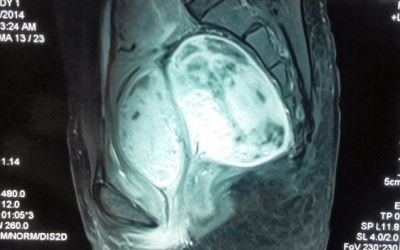

08/05/2014 14:24

Khi thai được 27 tuần tuổi, thấy có dấu hiệu đau bụng, chị Vũ Thị Vân đi khám mới tá hỏa mắc bệnh.